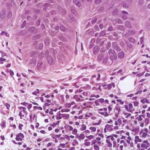

This variety of keratosis, sometimes referred to as florid keratosis, may easily be overdiagnosed as invasive squamous cell carcinoma by the unwary. Mild or moderate papillomatosis may be present. The epidermis is thickened in most areas and shows irregular downward proliferation that is limited to the uppermost dermis and does not represent frank invasion .A varying proportion of the keratinocytes in the stratum malpighii show a loss of polarity and thus a disorderly arrangement. Some of these cells show pleomorphism and atypicality (“anaplasia”) of their nuclei, which appear large, irregular, and hyperchromatic. Often the nuclei in the basal layer are closely crowded together. Some of the cells in the midportion of the epidermis show premature keratinization, resulting in dyskeratotic cells or apoptotic bodies characterized by homogeneous, eosinophilic cytoplasm with or without a nucleus. In contrast to the epidermal keratinocytes, the cells of the hair follicles and eccrine ducts that penetrate the epidermis within actinic keratoses retain their normal appearance and keratinize normally. Occasionally, cells of the normal adnexal epithelium extend over the atypical cells of the epidermis in an umbrella-like fashion. In some cases, abnormal keratinocytes extend downward on the outside of the follicular infundibulum to the level of the sebaceous duct and, less commonly, along the eccrine duct . |

A variant of the hypertrophic type of actinic keratosis is the lichenoid actinic keratosis, which demonstrates nuclear atypia, irregular acanthosis and hyperkeratosis, the presence of basal cell liquefaction, degeneration of the basal cell layer, and a bandlike “lichenoid” infiltrate in close apposition to the epidermis . Fairly numerous eosinophilic, homogeneous apoptotic bodies are seen in the upper dermis as so-called Civatte bodies. Aside from the presence of nuclear atypicality, |

In rare instances of actinic keratosis of the hypertrophic type, in addition to finding anaplastic nuclei in the lower epidermis, one finds areas of epidermolytic hyperkeratosis in the upper epidermis. These changes are like those seen in bullous congenital ichthyosiform erythroderma, in linear epidermal nevus, and as incidental epidermolytic hyperkeratosis in a variety of lesions. In areas of epidermolytic hyperkeratosis, one observes in the upper epidermis clear spaces around the nuclei and a thickened granular layer with large, irregularly shaped keratohyaline granules (39). Epidermolytic hyperkeratosis may occur also in lesions of solar cheilitis . |

The bowenoid type of actinic keratosis is histologically indistinguishable from Bowen’s disease and may also be referred to as squamous cell carcinoma in situ. As in Bowen’s disease, within the epidermis there is considerable disorder in the arrangement of the nuclei, as well as clumping of nuclei and dyskeratosis